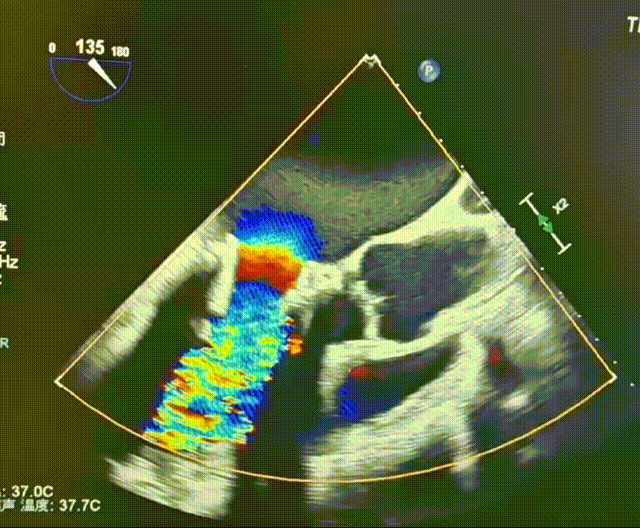

瓣架内径:25.0mm

瓣架外径:28.7mm

心室侧2mm:24.1mm

心室侧4mm:24.1mm

心室侧6mm:23.9mm

心室侧10mm:23.0mm

左房侧少量钙化

瓣架高度:约17.0mm

工作角度-瓣环切线位:RAO39°CRA38°

瓣下1.2mm处可见二尖瓣

LVOT:22.6mm,NEO-LVOT:23.5mm,模拟植入介入瓣后,流出道剩余面积尚可

TEE评估峰值流速仅0.8m/s

平均压差:术前18mmHg→ 术后3mmHg